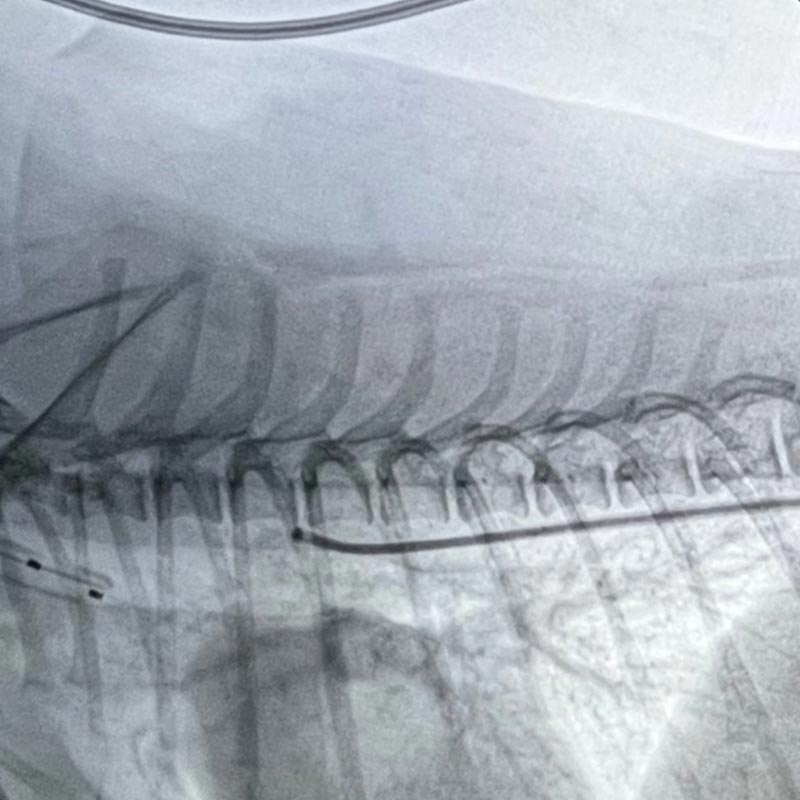

PDA (Patent Ductus Arteriosus)

코일 또는 디바이스 폐쇄술 (심장 안에서 기형 혈관 차단)

• 흉부 절개 없이 혈관을 통해 접근하여 수술 부담이 적음

• 정확한 위치에서 폐쇄시키기 때문에 재발 위험을 낮출 수 있음

• 회복이 빠르고 대부분 당일 혹은 단기간 입원이 가능함

PDA 폐쇄술

PDA 폐쇄술은 동맥관 개존증으로 열린 혈관을 코일 또는 디바이스를 통해 혈관 내에서 폐쇄시키는 인터벤션 시술입니다.

개흉 없이 카테터로 접근해 폐쇄하기 때문에 회복이 빠르고 합병증을 최소화할 수 있는 장점이 있습니다.